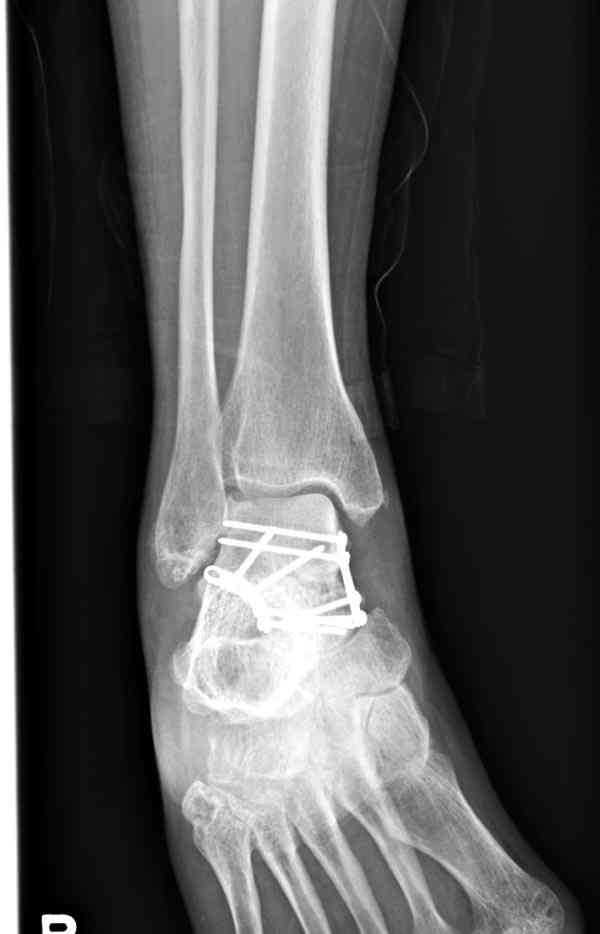

Случай с множественным оскольчатым переломом тарана оперированный из двойного доступа.

Через 2 мес.:

В вашем случае доступ через перелом медиальной лодыжки, обычный доступ через остеотомии лодыжки, где имеется возможность прямой репозиции тарана, после фиксации шурупами, лодыжки фиксируются обычным 2х лодыжечным методом.

При в первом типе придерживаемся закрытой репозиции, а у всех остальных в зависимости от смещения предпочитаем открытую репозицию, фиксация шурупами или пластиной. Пластина 2.4 мм более предпочтительна для удержания мелких костных осколков.